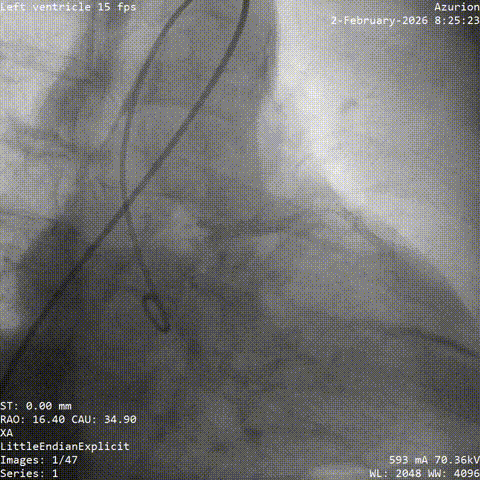

第一阶段,团队先为张老先生进行冠脉造影及介入治疗。结果显示,患者左前降支存在慢性完全闭塞病变,并伴有严重扭曲和钙化,常规处理难度较大。

在充分评估后,团队先对病变部位进行旋磨处理,再完成后续介入治疗。术后,张老先生病情稳定,未再出现心绞痛发作,也为后续主动脉瓣置换争取了更安全的条件。

CAG-LCA-1

CAG-LCA-2

CAG-RCA-1

CAG-RCA-2

▲冠脉造影:LAD-CTO病变,严重扭曲、钙化

▲开通,扭控MC

▲旋磨

▲术后